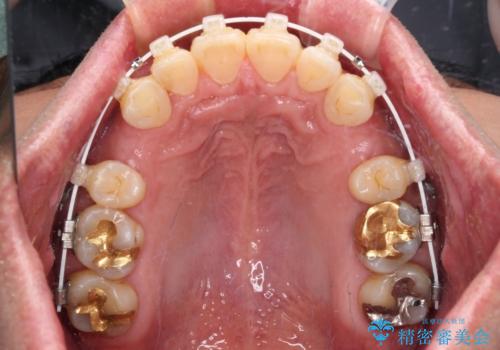

- 審美装置

- 口元の突出感を気にして来院された患者様です。

強い咬合力と上顎前歯の傾斜により前歯が突出し、唇が閉じにくい状況であったため、上下左右の第一小臼歯4本を抜歯し、ワイヤー装置にて矯正治療を行うこととしました。

非常に咬合力が強いため、抜歯したスペースが閉じるのか不安でしたが、順調に歯が移動し、予定よりも早く治療を終えることができました。